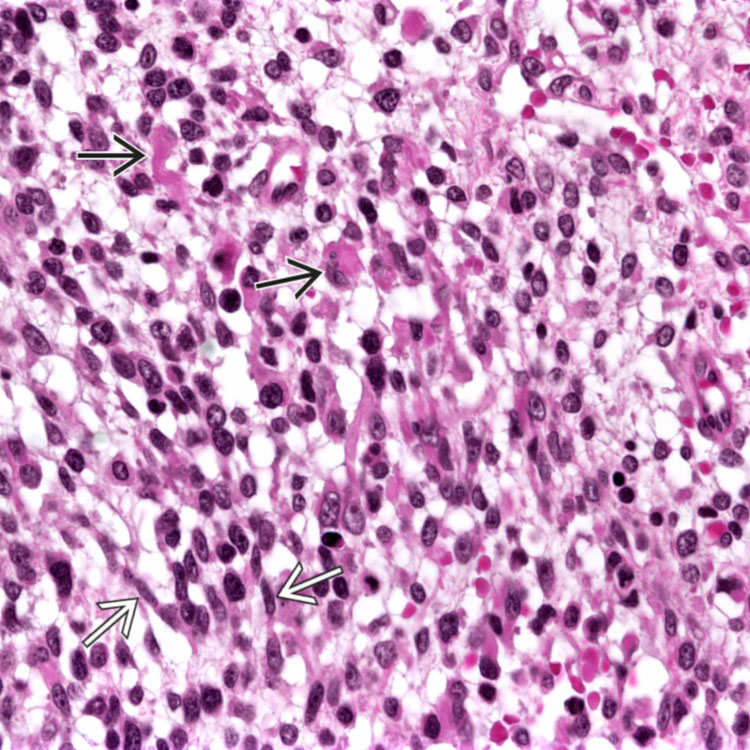

Embryonal Rhabdomyosarcoma Showing; (a) Several Rhabdomyoblasts Having

embryonal rhabdomyosarcoma cellularity appearances

embryonal rhabdomyosarcoma rms small cells tumor round hyperchromatic spindled typically ovoid